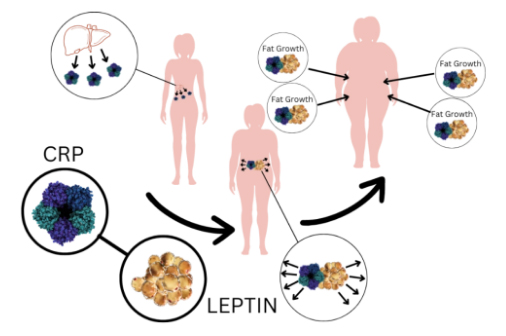

In short, no. If that was the case, all the diets and fitness programs attempted by millions of overweight people would work, wouldn’t it? There wouldn’t be so many stories of people who tried one diet or another and failed. And there wouldn’t be a need for the dozens and dozens of studies into the impact of leptin, cortisol, and insulin on your health … nor the studies of hormone-balancing ingredients like those found in Leptisense.

What will happen if I don't balance my hormones?

You run the risk of shortening your life by years, if not decades, by putting yourself at risk of heart disease, Type 2 diabetes, and metabolic syndrome.

Your blood sugar will still spike and drop, leaving you bouncing between intensely hungry and devastating tired every few hours…

Your sleep will suffer, as you gain more fat around your face, neck, and core …

You’ll continue to gain unattractive and unhealthy flab around your waist, hips, thighs, arms, and face …